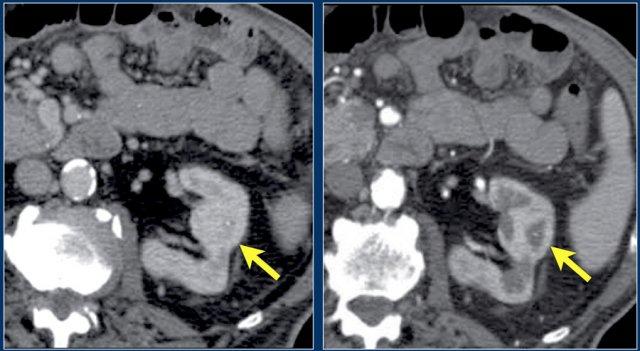

Trong trường hợp này, có các vùng giảm tỷ trọng ở cả hai thận.

Chỉ dựa trên hình ảnh, chẩn đoán phân biệt chính bao gồm viêm bể thận đa ổ, u lympho và di căn.

Bệnh nhân này có tiền sử nhiễm trùng đường tiết niệu, các đợt đau hông lưng và không có tiền sử u nguyên phát hay u lympho.

Do đó, chẩn đoán là viêm bể thận.

Chụp CT 4 tháng sau cho thấy sự ngấm thuốc bình thường của cả hai thận; các bất thường thận trên lần chụp đầu tiên do đó phù hợp với một đợt viêm bể thận đa ổ.